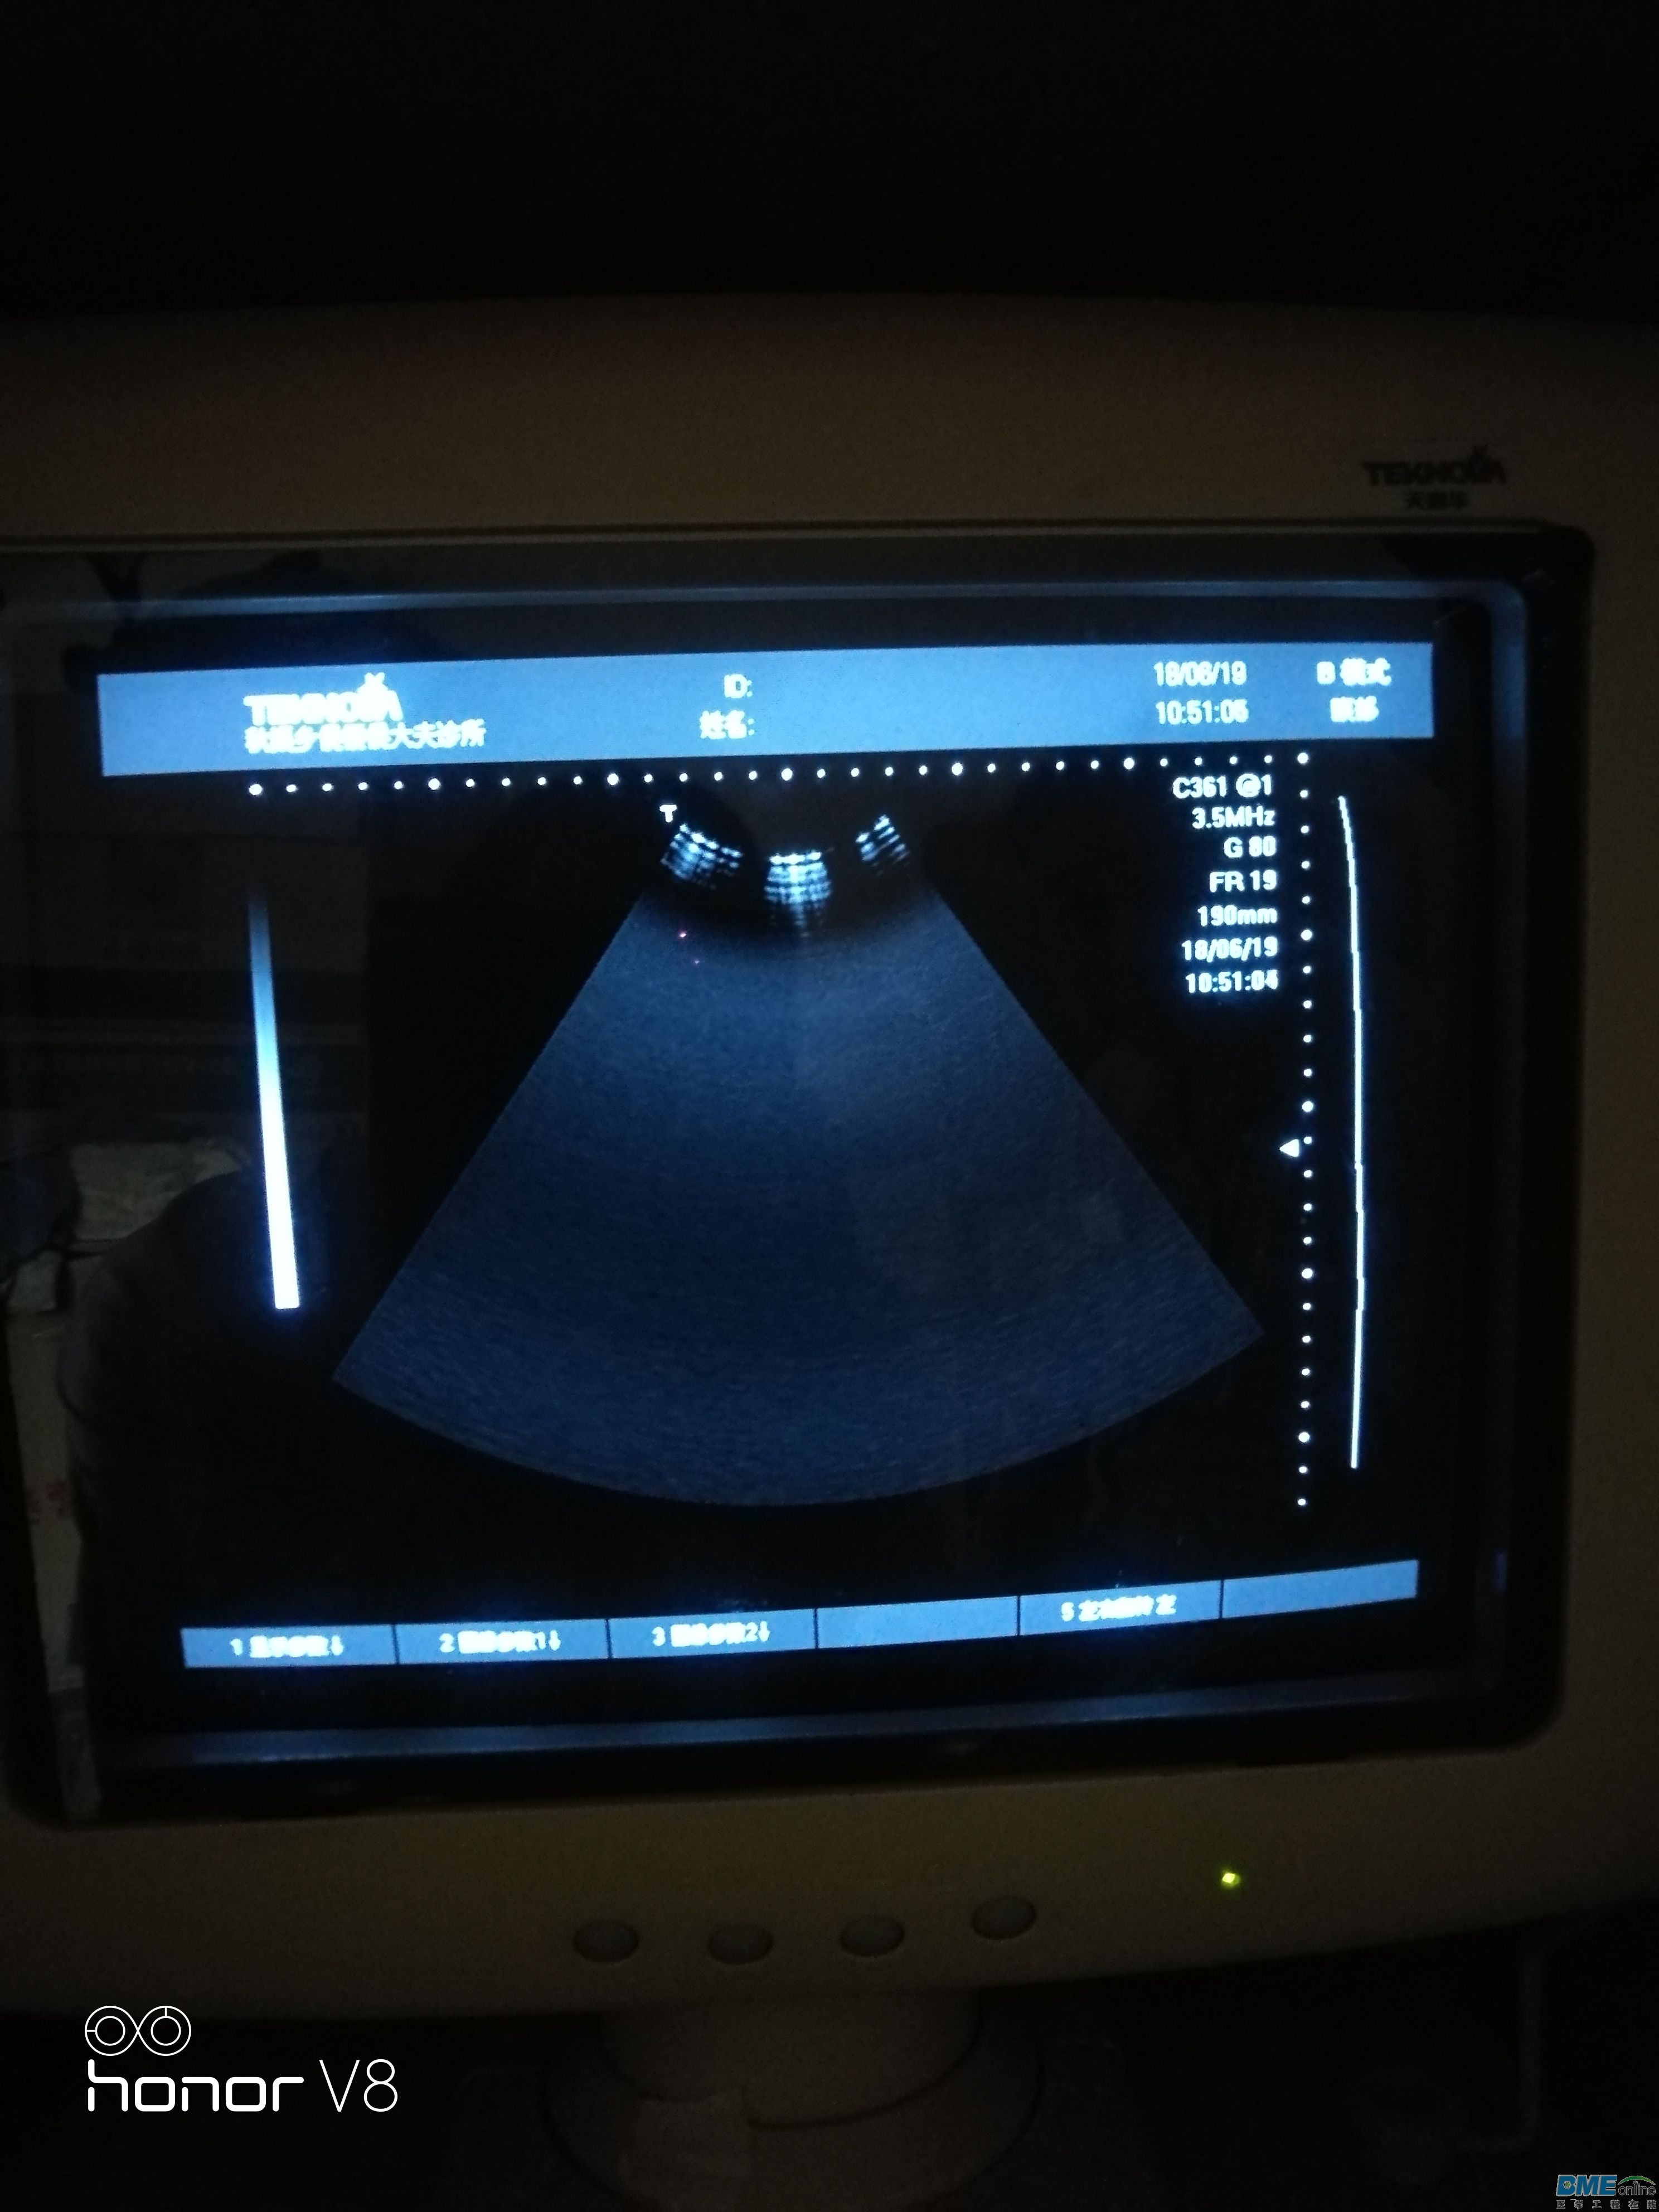

今天接收一台天惠华TH-200的B超级,问题是扇形区域里图像变小,如图扇形区域里只有上部分有图像,拔下探头图像不变。

,下面图是接入探头后直接测试腹部的图片,图上可以看出隐隐约约的影像探头接入后探测腹部扇形区域能有阴影的影像,开机拔去探头扇形区域只有一点点影像!求教维修思路